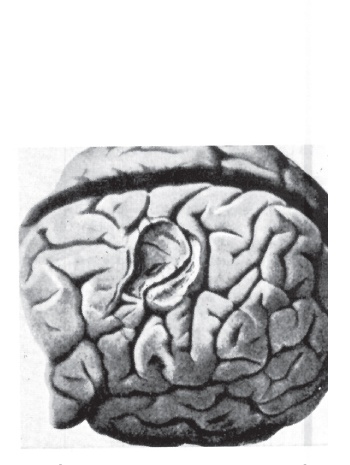

Бассини бросил в деревянный ящик платок, которым вытирал руки. Второй раз за несколько часов я заметил печальное выражение на его губах. «Мы, итальянские врачи, – проговорил он, – несмотря на то что обладаем славными медицинскими традициями, за последний век ничего не привнесли в общий научный прогресс, поэтому современная итальянская медицина поверхностна и отстала. Я только тогда выступлю с докладом о моей работе, когда на моем счету будет более двухсот пятидесяти успешных операций, чтобы никто из международных экспертов не смог сомневаться в моем методе. Только в этом случае я смогу послужить не только больным, но и моей стране». Он кивнул Тансини, и тот поднял мерцающую лампу с выступа в стене, которая простояла там все время демонстрации Бассини. Тансини первым ступил на лестницу, по которой мы спускались в подвал. За ним последовал Бассини. Последними шли мы и молчали. Все в этом доме было старо, мрачно и ветхо; формально это было связано с возрастом больницы и отсталостью. И все это не помешало человеку, чью худую и высокую фигуру я видел ступенькой выше, сделать открытие, которое привело бы в движение все медицинское сообщество, если бы только оно узнало о нем. «До утра, – коротко сказал Бассини и пожал нам с Гальманом руки. – В шесть». На этом он удалился в сопровождении Тансини. Я слышал стук каблуков его грубых ботинок еще с минуту, после звук совсем стих. Я не думаю, что когда-либо встречал итальянца более пунктуального, чем Бассини. Стрелки показывали ровно шесть, когда следующим утром он вошел в обставленный деревянной мебелью амфитеатр, где собирался оперировать. С его лица еще не сошел румянец после утренней конной прогулки. Гальман и я расположились в самом нижнем ряду амфитеатра, поблизости от операционного стола. Когда первого из двух пациентов, двадцатиоднолетнего Эрнесто Кальцаваре внесли, завернутого в пропитанные сублиматом простыни, в которых он провел всю ночь, Бассини попросил нас подойти к операционному столу. Ассистировал Тансини, как и за день до этого под сводами подвала. Два незнакомых молодых врача занимались наркозом и распылителем, струя пара из которого была направлена на паховую область пациента. Двое медсестер освобождали больного от простыней. Больной же почти сразу погрузился в глубокий сон, и Бассини начал операцию. Он действовал так же, как показывал на трупе. Вскоре перед нашими глазами оказалась новая, туго натянутая брюшная стенка. Бассини кивнул одному из молодых врачей. Последний взял перо и провел им по шее пациента. Сразу после этого у него возникли позывы ко рвоте. Все мышцы его живота напряглись. Я невольно приковал взгляд к брюшной стенке и свежим швам. Действительно ли они выдержат такое давление? Но я волновался напрасно. Поверхность оставалась тугой и неподвижной все время, пока длился приступ рвоты. Бассини мельком посмотрел на нас. Затем Тансини отпустил семявыводящий проток. Он поместил его на новую брюшную стенку, и Бассини, как и при операции на трупе, зашил над ним края апоневроза. Затем он наложил кожный шов, после – небольшую повязку. Бассини выпрямился, и на него обрушилась овация занимающих трибуны студентов. До конца июля 1888 года я оставался в Падуе, чтобы пронаблюдать за реконвалесценцией прооперированных. В самом конце июля окончательно поправившиеся Эрнесто Кальцаваре, Артуро Малатеста и Алоизи Марчиори покинули больницу. Двадцать второго июля к Бассини прибыл еще один больной грыжей, тридцативосьмилетний слуга из Монфеличе по имени Далла Валле, впоследствии успешно и без осложнений прооперированный. Но до этого времени я успел разыскать не менее сорока человек из ближних и дальных окрестностей Падуи, которые были прооперированы в течение прошедшего года. Блеск в их глазах развеял во мне все остававшиеся сомнения. Уже два, три и четыре года все без исключения прооперированные занимались своим привычным делом. Среди них были исключительно люди, выполнявшие тяжелую работу, которые не имели возможности следить за собой. Без сомнения, все они были теперь полностью здоровы. И такой стабильности не удавалось добиться еще никому в мире. Первого августа, покидая Падую, я был уверен, что паховая грыжа, этот кошмар, мучавший человечество тысячелетиями, была уже не так страшна. Я верил, что новая хирургическая методика через некоторое время, которое требовалось тогда на ее освоение, распространится из Италии по всему, как говорят, цивилизованному миру. Два года спустя Эдоардо Бассини в сороковом выпуске немецкого «Архива клинической хирургии» впервые подобающим образом описал свой метод и сообщил о не менее чем 262 операциях. И тогда будто бы распахнулась запертая дверь. Хотя Макивен в Англии и Хальстед в США приблизительно в то же время разработали новые способы хирургического лечения, причем предложенное Хальстедом решение было сродни методу Бассини, Падуя стала меккой для многочисленных хирургов, которые хотели последовать по пути, намеченному итальянцем. Оригинальный метод наравне с несколько измененным и улучшенным стал началом хирургии грыжи, достигшей в будущем больших высот. ![]() Луи Пастер (1822–1895). Его работы о природе гниения побудили Листера к созданию антисептики. На рисунке изображен Пастер среди клеток с его подопытными животными ![]() Великий переворот: операционная знаменитого американского хирурга Гросса (1805–1884) до появления асептики ![]() Джон Стау Боббс (1809–1970), один из хирургов «Дикого Запада», работавший в штате Индианаполис. Он вскрыл брюшную полость портнихи Мери Э. Уиггинс с намерением обнаружить там опухоль и, не догадываясь о том, провел первую операцию на желчном пузыре ![]() Уильям Макивен (1848–1924), хирург, которому впервые удалось вскрыть абсцесс головного мозга и остановить мозговое кровотечение ![]() Рикман Годли (1849–1925) 25 ноября 1885 года провел первую операцию по удалению опухоли головного мозга ![]() Жан Мартен Шарко (1825–1893), известнейший французский невропатолог своего времени ![]() Модель головного мозга после удаления опухоли. Отчетливо видно углубление, откуда опухоль была вылущена |